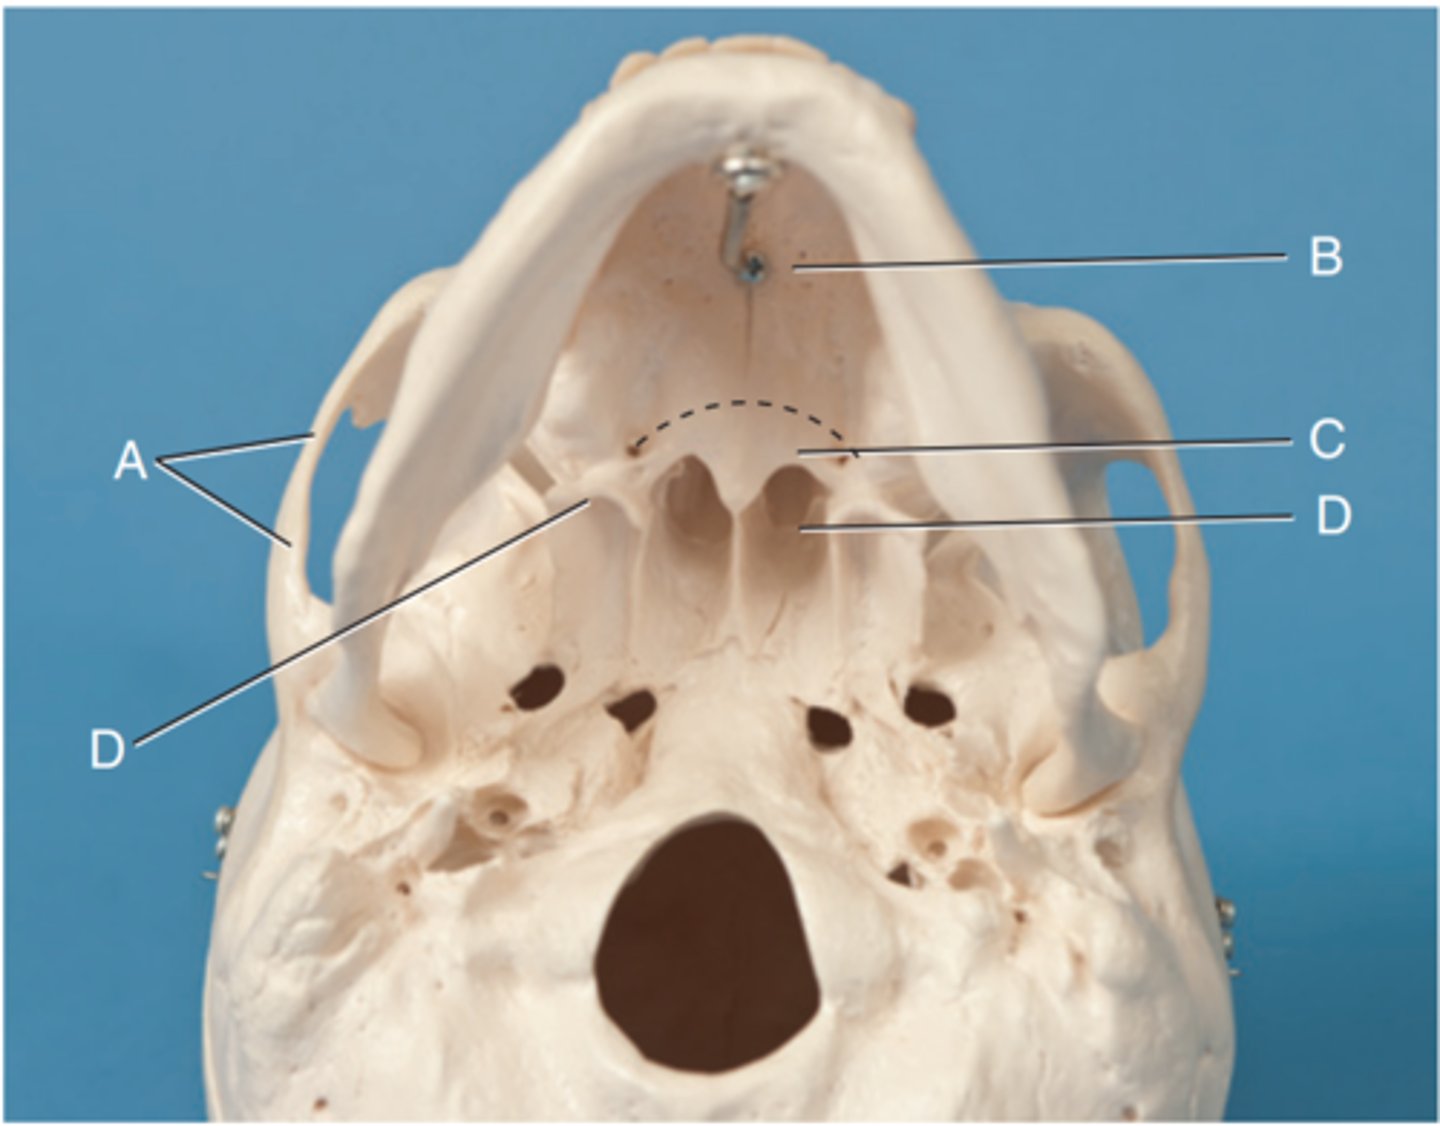

Label A

Posterior clinoid processes

Label B

Petrous ridge or petrous pyramid

Label C

Parietal bone

Label D

Occipital bone

Label E

Foramen magnum

Label F